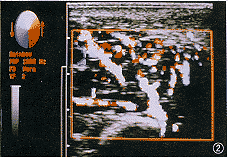

(1)混合瘤:形态呈圆形或结节状,边界尚清楚,内部回声为暗淡粗光点,不均匀,占36例(56.3%)(图1);伴散在极小液区(液性暗区)者22例(34.4%);近中部伴较大不规则液区者6例(9.4%)。

图1 腮腺内混合瘤 血流Ⅰ级